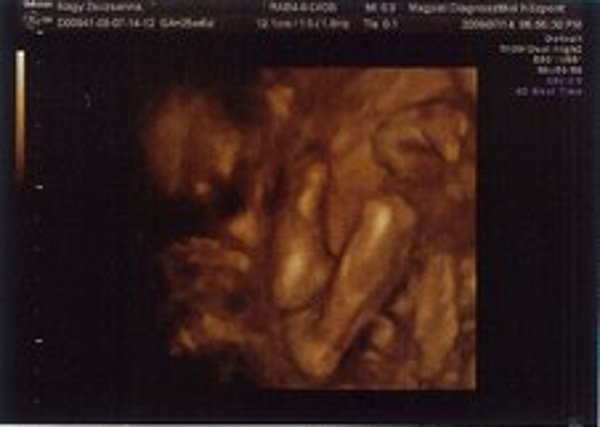

Nézzétek a kukim:

Kép

Zsuzska

Milyen édes kis arcocskája van :)

Édes kis turcsi orra lesz, mint apukájának van.... anyum szerint tiszta apja :lol: :lol: :lol: :lol: :lol: :lol: :lol: :lol:

Benőkéd már most jelentős mérettel rendelkezik, mi lesz később? :lol:

Amúgy nagyon édibogyó! :D

Jajj de szép Benőke! :) És tényleg látszik a kis kukija. :) Jajj meg azok a csöpp kis lábacskák! :) Na és a kis pofija... :) Megvallom könny szökik a szemembe... Hogy mennyire várom már, hogy láthassam a teljes valójában! :) GOndolom te még jobban.:)

Leírhatatlan érzés volt látni ilyen formában is. Anyum szerint már most tiszta apja a gyerek :lol: :lol: :lol: :lol: :lol: :lol: :lol: :lol:

Hát igen, apja méreteire hajaz a drágám úgy látszik :shock: :shock: :shock: :shock: :shock: :shock:

Végleges név még mindig nincs.

Most a Levente és a Bence a menő nálunk, de apa még mindig nem döntött :shock: :shock: :shock: :shock: :shock: :shock: